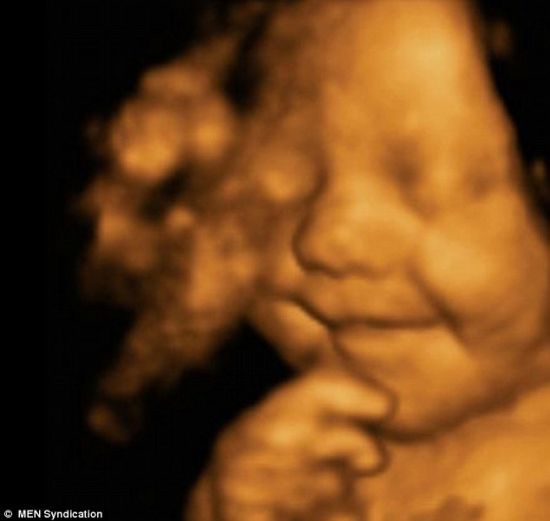

宝宝从出生前到出生后,一直笑嘻嘻乐呵呵的,显得相当幸福

在孩子母亲怀孕31周时,她曾前往医院做了超声波成像,然而令她和她丈夫惊讶的是,自己肚子中的宝宝一直乐呵呵地微笑着。